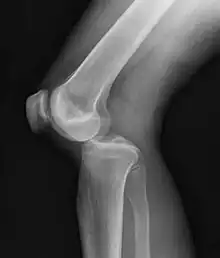

Plain X-rays, CT scan, ultrasonography, or MRI may help with the diagnosis.[2][11] Findings on X-ray that may be useful among those who have already reduced include a variable joint space, subluxation of the joint, or a Segond fracture.[5]

They may be divided into five types: anterior, posterior, lateral, medial, and rotatory.[4] This classification is based on the movement of the tibia with respect to the femur.[11] Anterior dislocations, followed by posterior, are the most common.[2] They may also be classified on the basis of which ligaments are injured.[2]